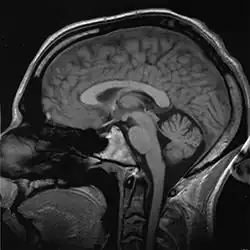

A T1-weighted MRI scan of a human head, an example of a biomedical engineering application of electrical engineering to diagnostic imaging. Click here to view an animated sequence of slices.

Imaging technologies are often essential to medical diagnosis, and are typically the most complex equipment found in a hospital including: fluoroscopy, magnetic resonance imaging (MRI), nuclear medicine, positron emission tomography (PET), PET-CT scans, projection radiography such as X-rays and CT scans, tomography, ultrasound, optical microscopy, and electron microscopy.